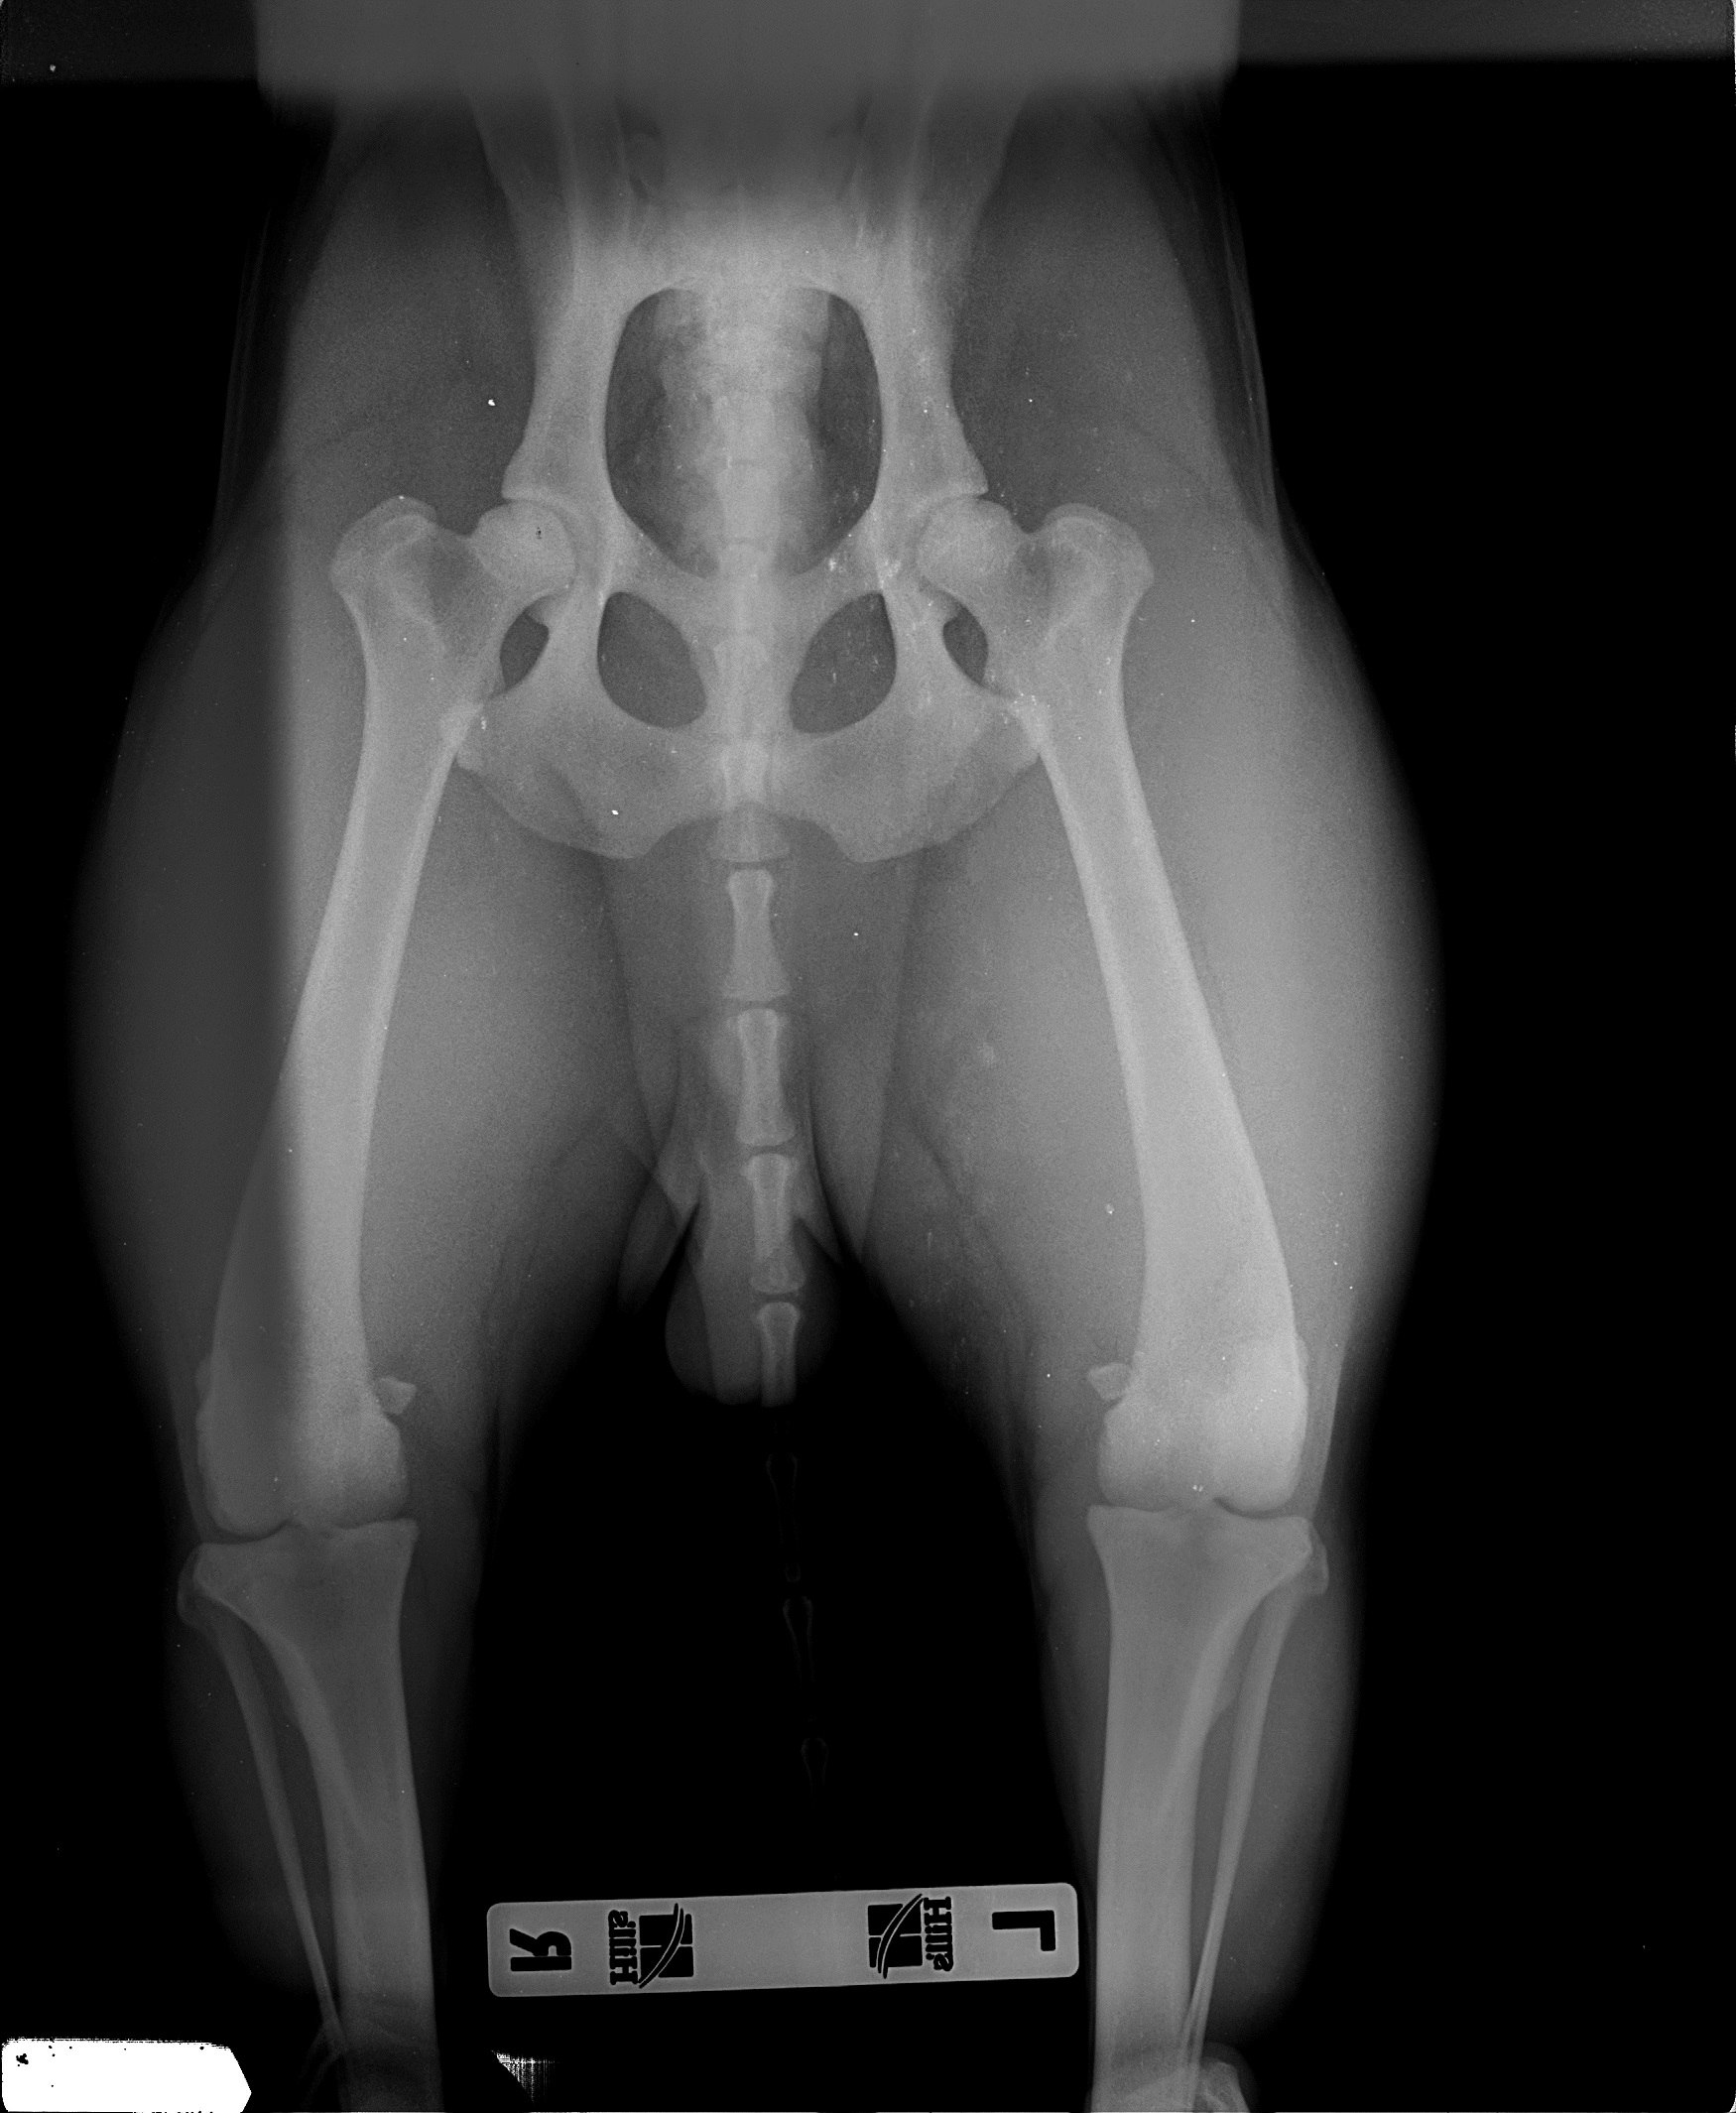

Рентген ТБС: Нормальные показатели

Раздел: Необычные решения